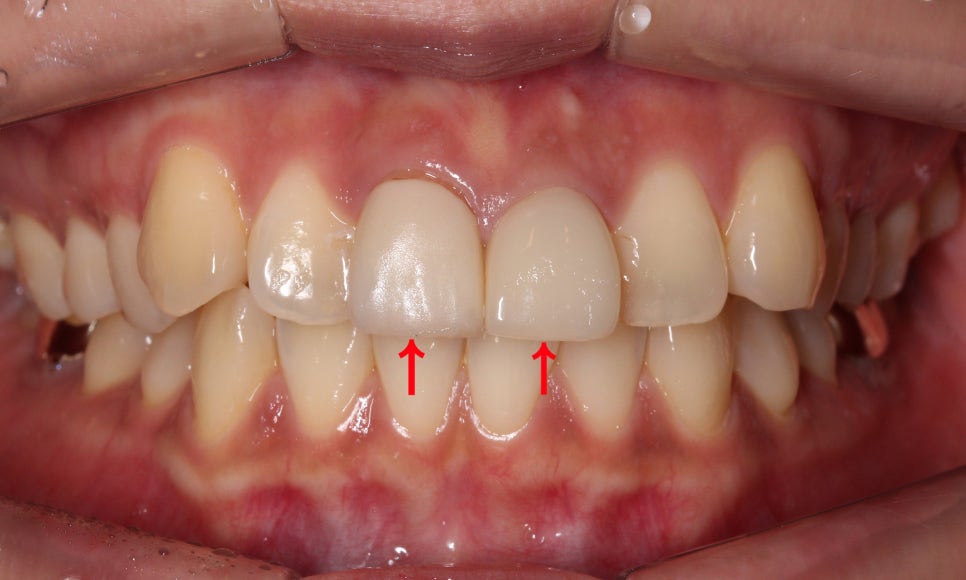

위의 토끼앞니 case는

상악 중절치에 PFM크라운

치료를 진행한 모습으로

정면에서 봤을 때 중절치의

돌출감이 있고 전체적인 치열이

삐뚤삐뚤한 모습입니다.